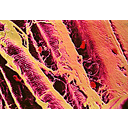

tessuto muscolare liscio.jpg